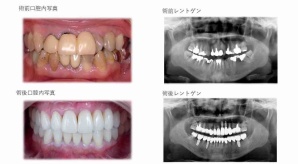

¥¤¥ó¥¹¥¿¥°¥é¥à¤ËºÜ¤»¤Æ¤¤¤ëÅö±¡¤Î¾ÉÎã¤Ç¤¹

ðÌî»õ²Ê¾ÉÎ㢠ÀèÅ··ç»¶ºÀµ¥¤¥ó¥×¥é¥ó¥È

ðÌî»õ²Ê¾ÉÎã¡¶ºÀµ¥¤¥ó¥×¥é¥ó¥È¥»¥é¥ß¥Ã¥¯